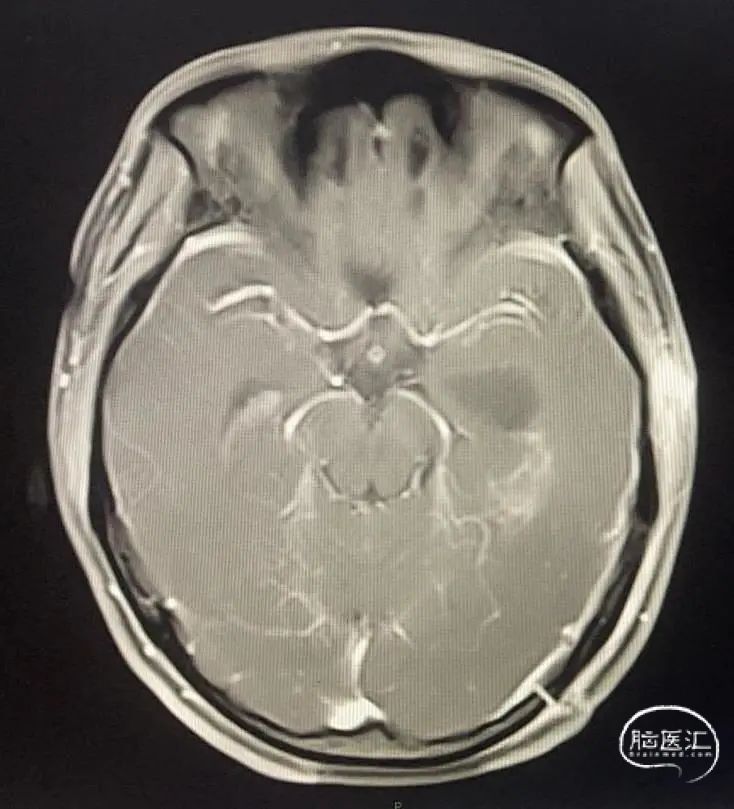

2021-10-25日由段剑副主任主刀行左侧脑室脑膜瘤切除术,手术顺利,2021-10-26日复查MRI示(图6)左侧脑室脑膜瘤切除满意。

图6